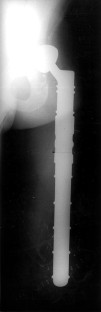

Fig. 1